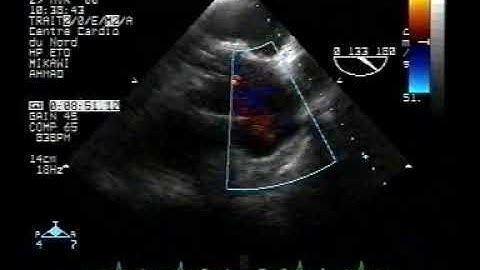

echocardiogram tee:localized dissection 1/3of the ascending aorta